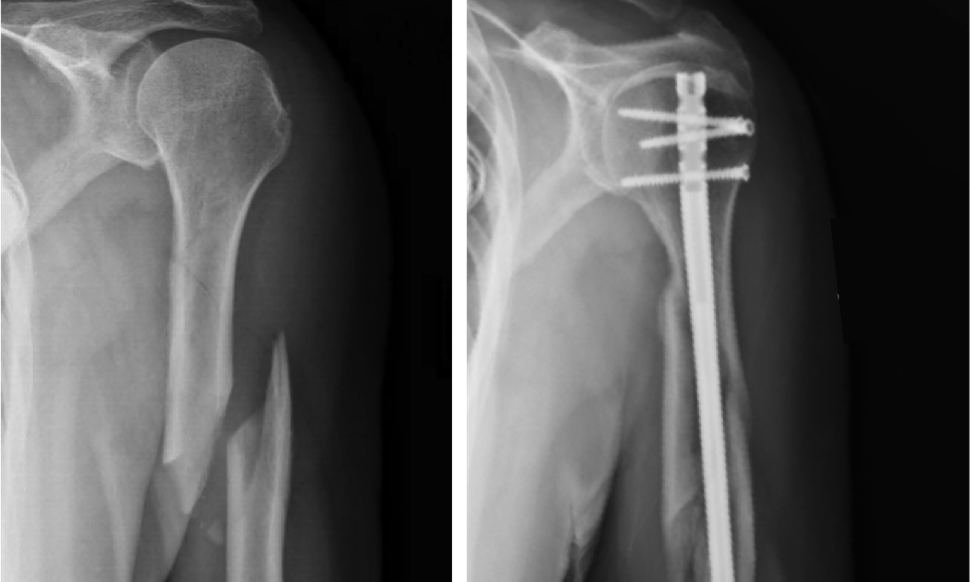

• Хирургическое лечение переломов плечевой кости и технических точек

Хирургическое лечение переломов плечевой кости и технических точек

2022-10-14

Переломы ножки плечевой кости (HSF) относительно распространены, на их долю приходится от 1% до 5% всех переломов.Ежегодная заболеваемость составляет от 13 до 20 на 100 000 человек, и было обнаружено, что она увеличивается с возрастом. HSF имеет бимодальное возрастное распределение, при этом первый пик приходится на мужчин в возрасте от 21 до 30 лет.